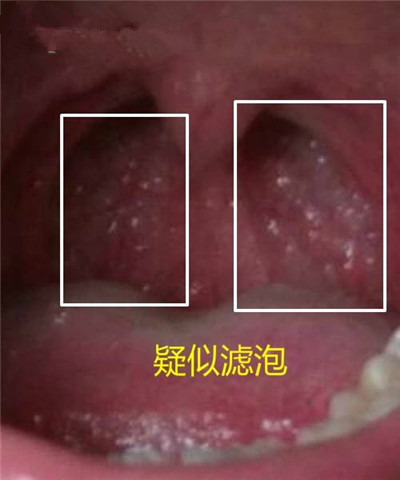

慢性咽喉炎圖片

喉部淋巴濾泡增生 (46)